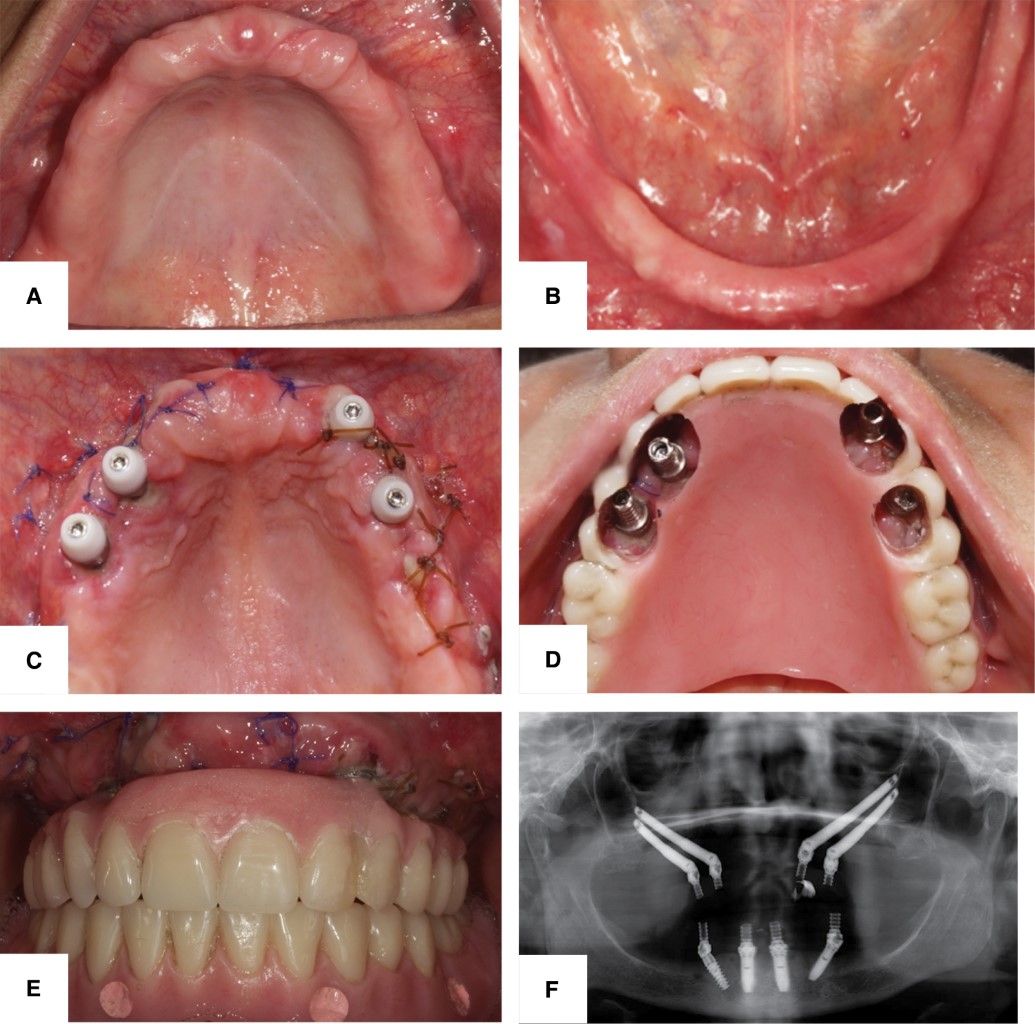

Se presenta un caso clínico de paciente femenino de 57 años (Figura 3A) de edad desdentada total (maxilar y mandíbula) (Figura 4A y 4B), sin datos patológicos relevantes para el padecimiento actual. La paciente acudió al Servicio de Implantología de la División de Estudios de Postgrado e Investigación (DEPeI, UNAM) para valoración y tratamiento. Se realizó la evaluación clínica, radiográfica y tomográfica, en la cual se obtuvo un diagnóstico de atrofia maxilar severa (Figura 2B). Se planteó la colocación de cuatro implantes cigomáticos para rehabilitación con prótesis fija híbrida. El procedimiento se llevó a cabo sin complicaciones bajo anestesia general previo protocolo para pacientes que requieren hospitalización. Se decidió realizar carga temprana (una semana después) con la prótesis inmediata que se confeccionó previamente.

Se colocaron cuatro implantes cigomáticos intrasinusales, mediante incisión lineal de espesor total, se localizó el agujero y nervio infraorbitario, se diseñó una ventana sinusal y se comenzó el protocolo de fresado, iniciando con una fresa de bola, se colocaron los implantes cigomáticos en los cuales se obtuvo 35 Ncm de torque; posteriormente se colocaron los Multi-Unit y en este caso se decidió dejar la carga inmediata para 10 días posteriores a la cirugía (carga temprana). A los 10 días se presentó la paciente a la clínica y se rehabilitó de forma provisional (Figura 4C-4E). Para complementar su tratamiento en la mandíbula se decidió colocar cuatro implantes (All on Four). En la ortopantomografía se observaron implantes en posición y cumpliendo función (Figura 4F). En el momento de la colocación de la prótesis es considerable el cambio que se observó en el aspecto físico de la paciente (Figura 3B).